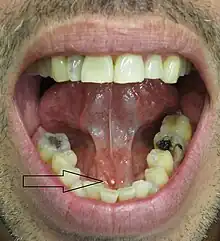

Sialolithiasis (also termed salivary calculi,[1] or salivary stones)[1] is a crystallopathy where a calcified mass or sialolith forms within a salivary gland, usually in the duct of the submandibular gland (also termed "Wharton's duct"). Less commonly the parotid gland or rarely the sublingual gland or a minor salivary gland may develop salivary stones.

Salivary stones may be divided according to which gland they form in. About 85% of stones occur in the submandibular gland,[3] and 5–10% occur in the parotid gland.[2] In about 0–5% of cases, the sublingual gland or a minor salivary gland is affected.[2] When minor glands are rarely involved, caliculi are more likely in the minor glands of the buccal mucosa and the maxillary labial mucosa.[4] Submandibular stones are further classified as anterior or posterior in relation to an imaginary transverse line drawn between the mandibular first molar teeth. Stones may be radiopaque, i.e. they will show up on conventional radiographs, or radiolucent, where they not be visible on radiographs (although some of their effects on the gland may still be visible). They may also symptomatic or asymptomatic, according to whether they cause any problems or not.

- Palpable hard lump, if the stone is located near the end of the duct.[1][3] If the stone is near the submandibular duct orifice, the lump may be felt under the tongue.